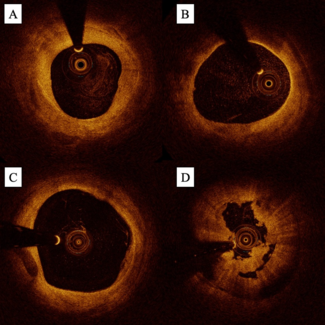

The authors review the applications and supporting data for the use of intravascular ultrasound and optical coherence tomography in infrainguinal endovascular intervention.